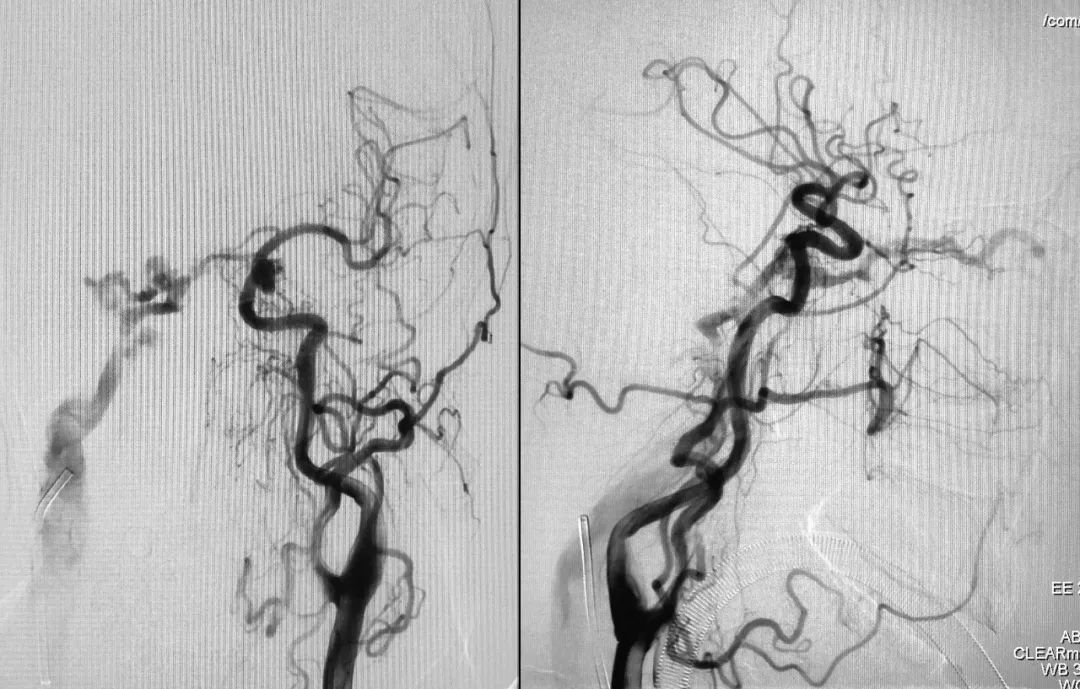

右侧颈总动脉正、侧位造影:

左侧颈总动脉正、侧位造影:

右侧颈内动脉正、侧位造影: